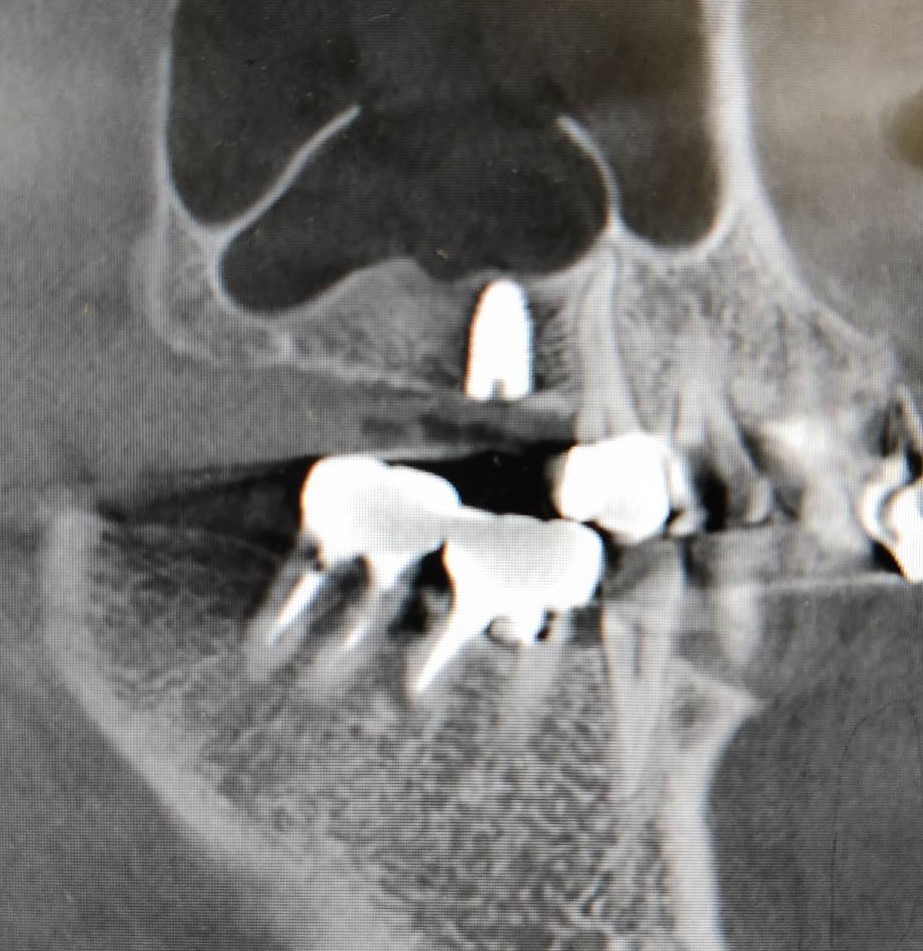

上顎洞底挙上術を併用したインプラント埋入の症例紹介

Before

After

6か月後

インプラント埋入

主訴

右上奥歯にインプラントを入れたい。

治療内容

右上奥歯の骨が薄いため、まず人工骨を用いて造骨しました。6か月後に骨ができたのでインプラントを埋入しました。

治療費

上顎洞底挙上術:165,000円(税込)

インプラント埋入術:220,000円(税込)

治療期間

7か月

通院回数

5回

想定されたリスク

※上顎洞粘膜穿孔、上顎洞炎、腫脹、内出血、鼻出血の可能性がありました。

石毛 俊作先生

大神宮デンタルクリニック

インプラントを埋入する際に十分な骨量がない場合は骨造成を行います。骨造成の方法は症例によって異なりますが、今回のケースは上顎洞底挙上術を用いました。